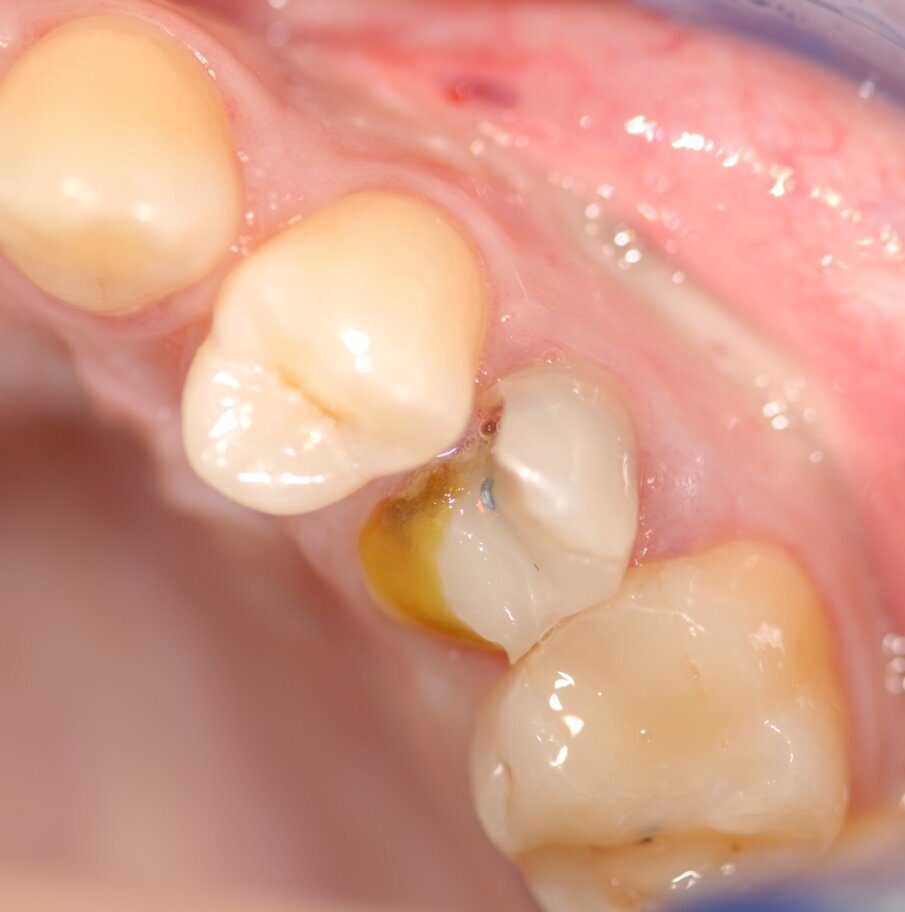

La paziente presentava un primo premolare superiore sinistro non recuperabile. La CBCT mostra la situazione iniziale (Fig. 1). Si noti quella che appare come una grande fenestrazione buccale nell’area della resezione radicolare (Fig. 2). Il dente fratturato è stato estratto (Figg. 3, 4). Lo scollamento del lembo di accesso rivela la fenestrazione buccale (Fig. 5). L’osteotomia è stata preparata secondo il protocollo di fresatura di Neoss ProActive Edge (Fig. 6). Successivamente viene posizionato un impianto Neoss ProActive Edge Ø 5.0 × 13 mm (Fig. 7). L’impianto è stato posizionato in una situazione di disponibilità ossea molto limitata e densità ossea media (Fig. 8). Nonostante le limitazioni dovute alla condizione ossea, è stata raggiunta una buona stabilità primaria. È stato utilizzato un torque di inserimento di 20 Ncm, l’ISQ è risultato in un range di 70/77. Per correggere la fenestrazione buccale è stato eseguito un innesto con particolato osseo di origine porcina (Fig. 9). L’innesto osseo è stato coperto con una membrana di collagene riassorbibile (Fig. 10). Il lembo mucoso è stato suturato attorno al pilastro di guarigione in PEEK, consentendo la guarigione in una sola fase (Fig. 11).